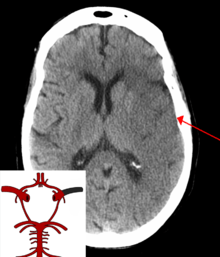

The main risk factor for stroke is high blood pressure.[4] Other risk factors include tobacco smoking, obesity, high blood cholesterol, diabetes mellitus, previous TIA, and atrial fibrillation.[2][4] An ischemic stroke is typically caused by blockage of a blood vessel.[5] A hemorrhagic stroke is caused by bleeding either directly into the brain or into the space surrounding the brain.[5][6] Bleeding may occur due to a brain aneurysm.[5] Diagnosis is typically with medical imaging such as a computerized axial tomography (CT) scan or magnetic resonance imaging (MRI) scan along with a physical exam. Other tests such as an electrocardiogram (ECG) and blood tests are done to determine risk factors and rule out other possible causes. Low blood sugar may cause similar symptoms.[7]

Stroke is diagnosed through several techniques: a neurological examination (such as the NIHSS), CT scans (most often without contrast enhancements) or MRI scans, Doppler ultrasound, and arteriography. The diagnosis of stroke itself is clinical, with assistance from the imaging techniques. Imaging techniques also assist in determining the subtypes and cause of stroke. There is yet no commonly used blood test for the stroke diagnosis itself, though blood tests may be of help in finding out the likely cause of stroke.[52]

Imaging

For diagnosing ischemic stroke in the emergency setting:[53]

- CT scans (without contrast enhancements)

- sensitivity= 16%

- specificity= 96%

- MRI scan

- sensitivity= 83%

- specificity= 98%

For diagnosing hemorrhagic stroke in the emergency setting:

- sensitivity= 89%

- specificity= 100%

- sensitivity= 81%

For detecting chronic hemorrhages, MRI scan is more sensitive.[54]